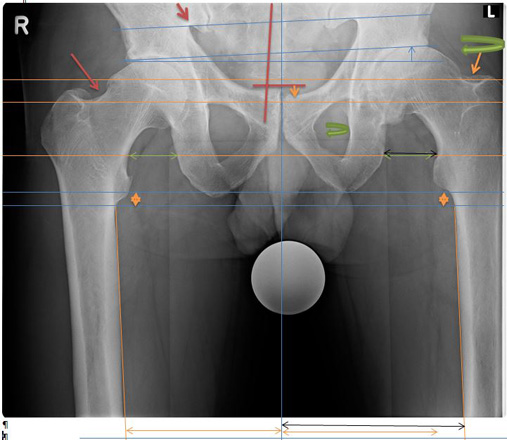

Becken Bild 1

Anhand der Original Aufnahmen werden Spannungsbedingte Ausweichhaltungen auf den folgenden Seiten sichtbar gemacht.

6848180

1.1

Aufnahme zeigt eine Verdrehung der linken Seite, anhand der Beckenlöcher.

Zudem muss das Becken seitlich verschoben sein.

Sichtbar anhand der Beinstellungen und der Verdrehung des Schenkelhalses.

Weiter wird ersichtlich, dass links das Becken hochgedrückt wird.

Eindeutig am Beckenspalt zu erkennen, das der Oberkörper nach links ausweicht und somit das Becken in der Höhe verzieht.

Auch drückt es oberhalb der Hüftkugel rechts das Becken über den Zug der seitlichen Oberkörper Haltung hoch und verzieht das Becken.